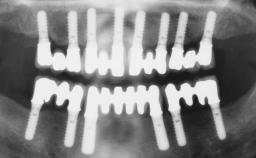

# of Teeth | 3 |

# of Implants | 3 |